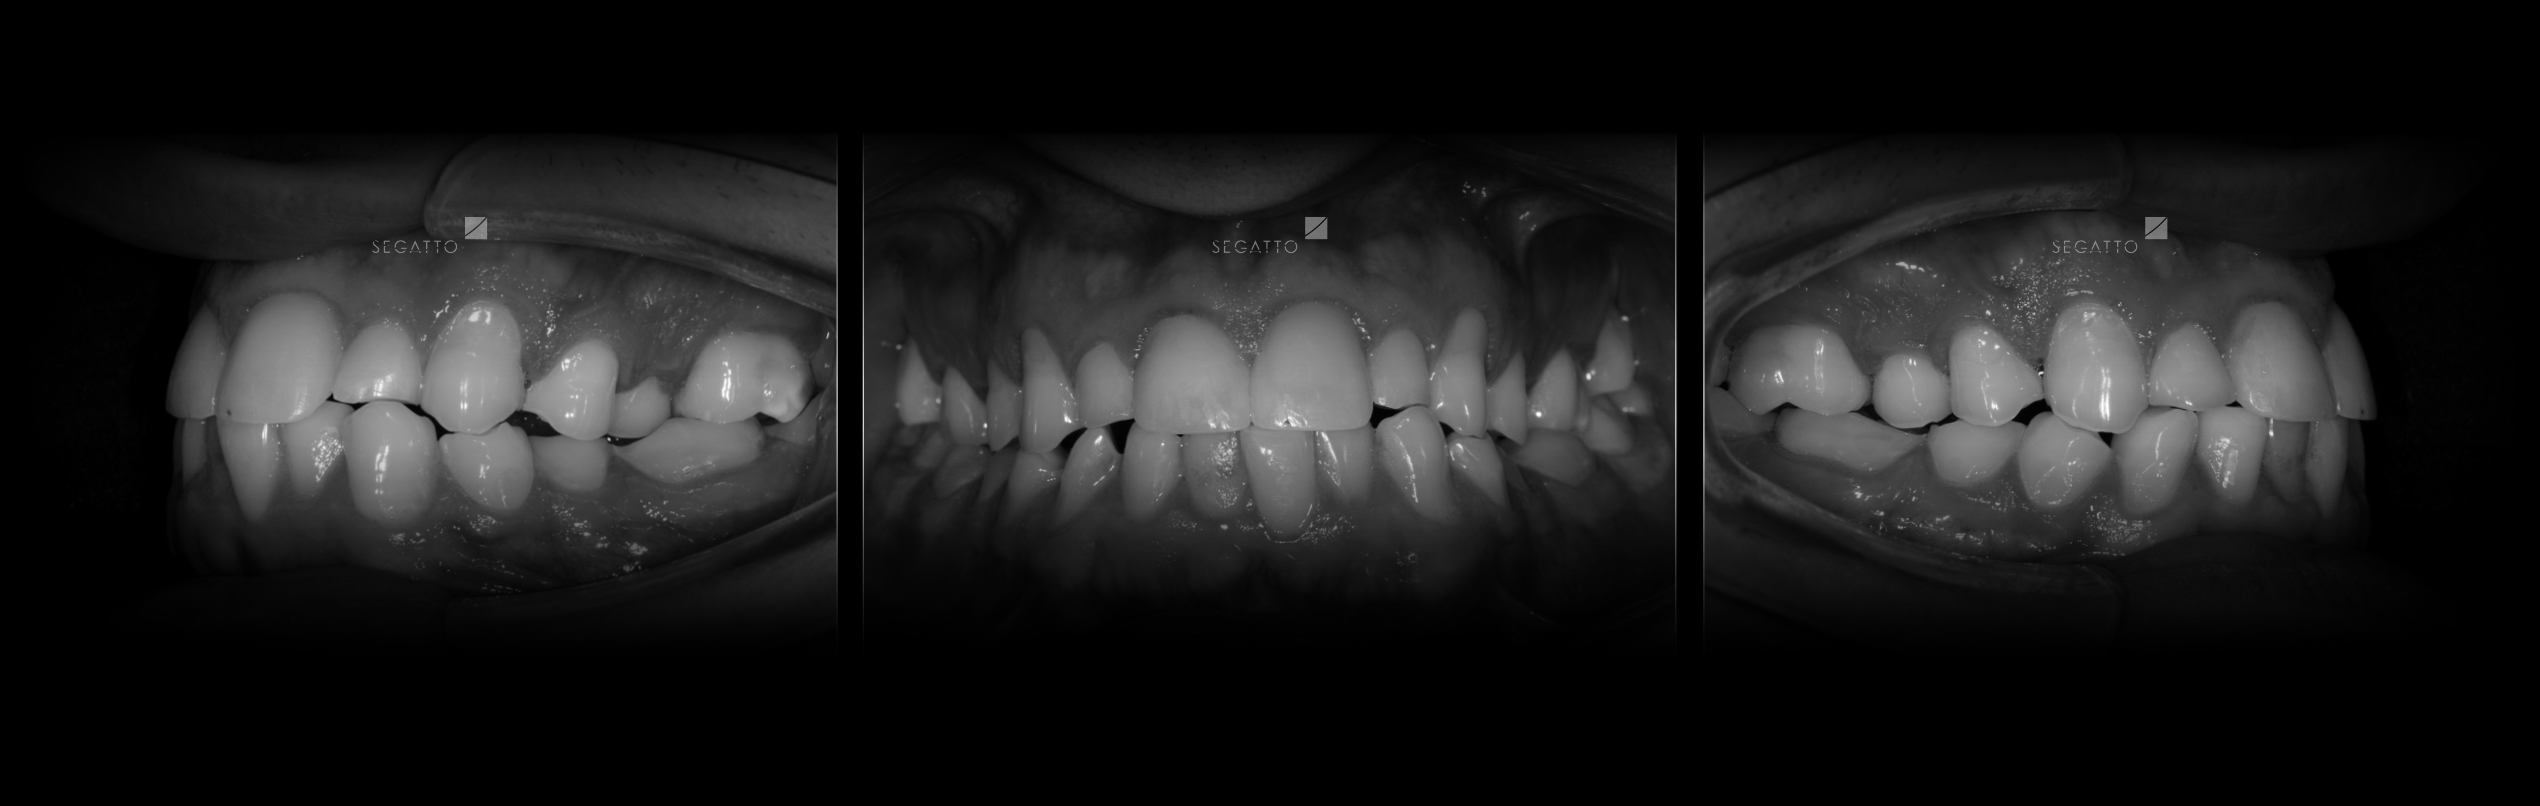

Orthodontics

Cases